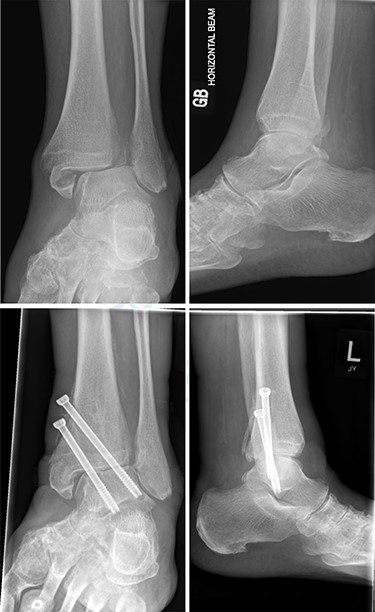

Overall, four out of six patients (66.7%) had satisfactory post-op radiographs with no evidence of talar shift, non/mal-union, widening of the syndesmosis or screw loosening (Figs 1 and 2).

Top—Fracture dislocated bimalleolar ankle fracture. Bottom—6 weeks post-operatively showing maintained tibiotalar alignment.